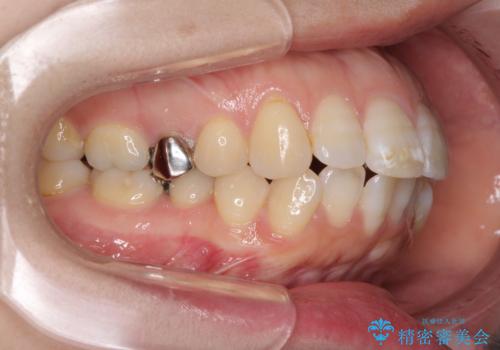

- 口元の閉じにくさと、前歯のでこぼこの歯並びを気にして来院された患者様です。

口元を積極的に引っ込めるために、上下左右の小臼歯計4本を抜歯することとしました。

セオリーでは第一小臼歯を抜歯しますが、上下右側は第二小臼歯に銀歯が装着されているため、第二小臼歯を抜歯することとしました。